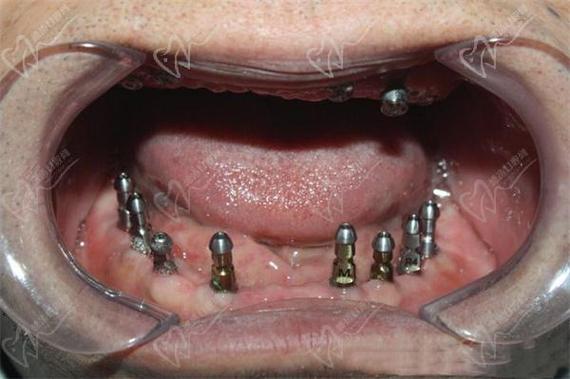

(图片来源网络,侵删)- 在局部麻醉下进行。

- 根据方案,在牙槽骨中精确植入预定数量(通常4-6颗)的种植体。

(图片来源网络,侵删)- 当种植体稳定愈合后,医生会安装取模基台,取牙齿的精确模型(或使用口内扫描仪数字化获取模型)。